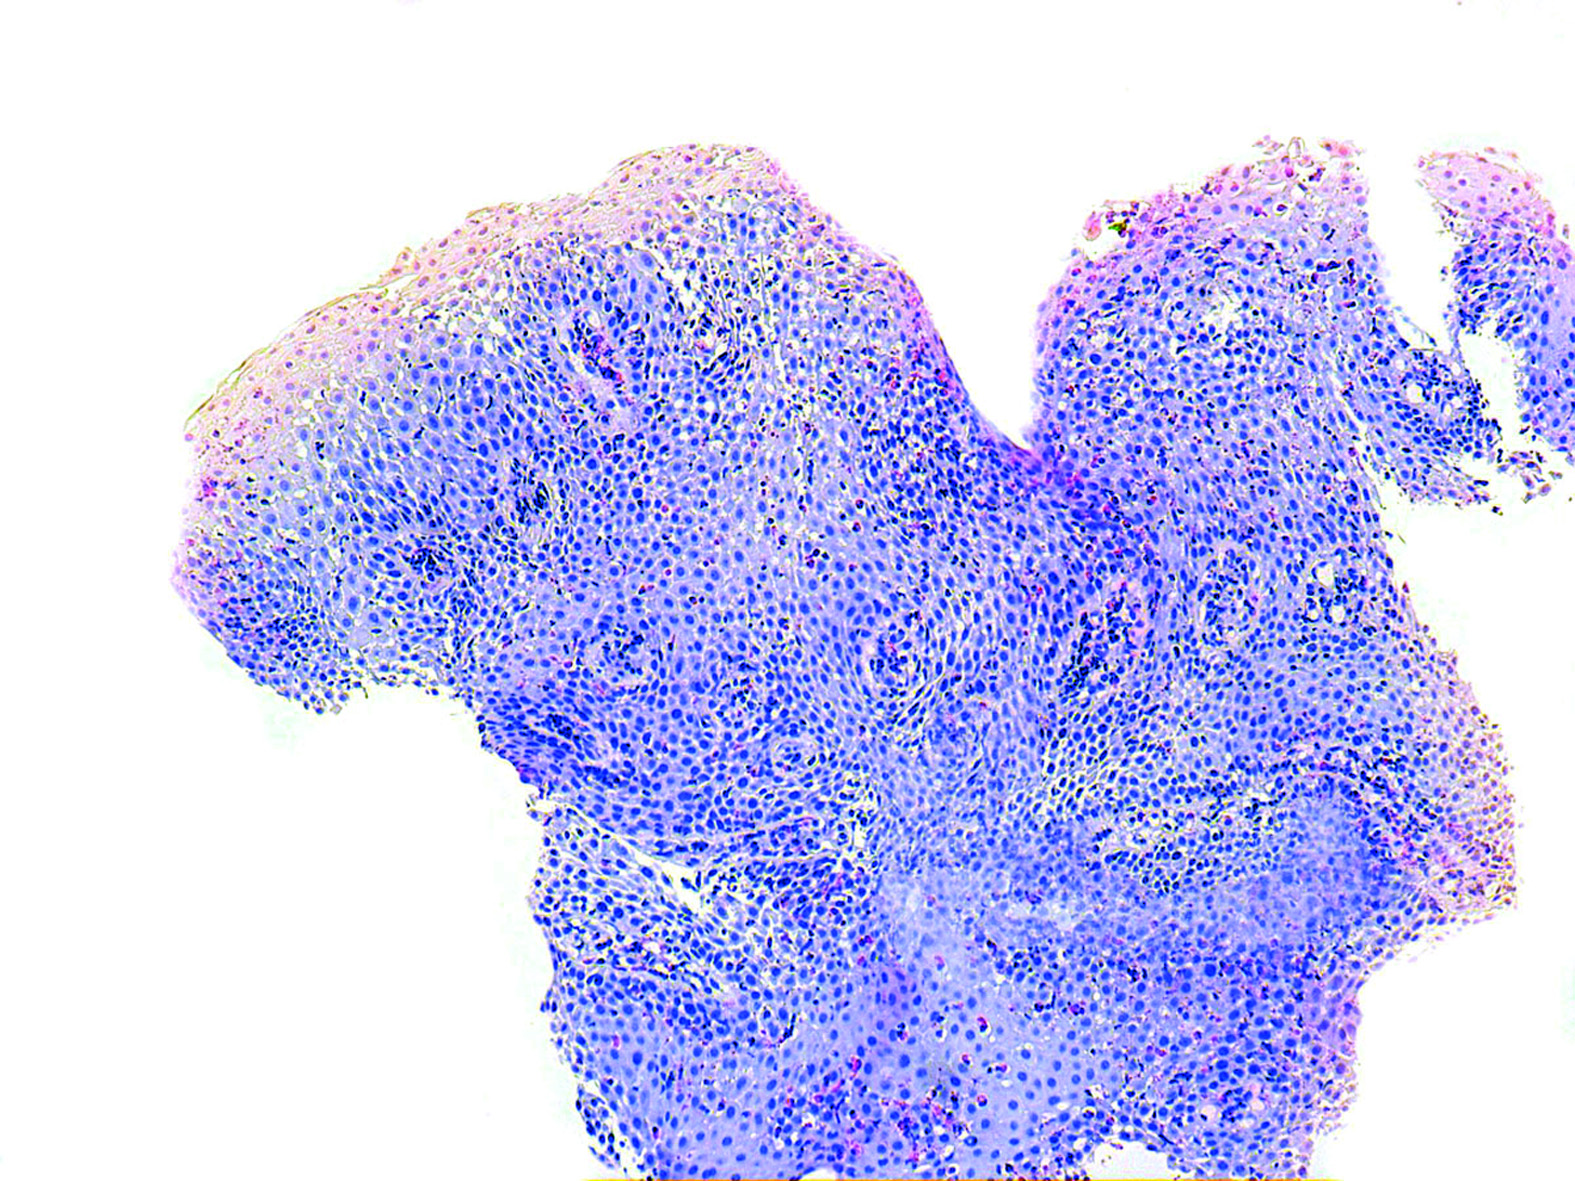

La esofagitis eosinofílica (EE) es una enfermedad caracterizada por la infiltración de la mucosa del esófago por eosinófilos, cuya incidencia en adultos parece estar aumentando en los últimos años, de forma similar a lo que ocurre en otras enfermedades de probable etiología inmunoalérgica. Predomina en varones jóvenes y se manifiesta principalmente por disfagia e impactación alimentaria. Su tratamiento se basa en eliminar el alérgeno potencialmente implicado y la administración de corticoides. En el presente trabajo se revisan retrospectivamente los casos de EE diagnosticados en el Hospital de Navarra entre enero de 2002 y agosto de 2008, encontrándose 25 pacientes, lo que supone una incidencia de 2,13 casos/105 habitantes/año. Un 72% de nuestros pacientes presentaban disfagia y un 52% historia de impactación del bolo alimentario, encontrándose alteraciones endoscópicas en 23 de los 25 casos. De 24 pacientes estudiados, un 76% manifestaban alergia alimentaria o a neumoalérgenos, lo que apoya el fondo inmunoalérgico de la enfermedad y la necesidad de un estudio alergológico en todos las pacientes con EE. La mayoría de nuestros pacientes (22 de 24 valorados) presentaron buena respuesta clínica al tratamiento, que se basó en evitar la exposición al alergeno potencialmente implicado y/o la administración de corticoides (tópicos o sistémicos) y/o la administración de inhibidores de la bomba de protones.Descargas